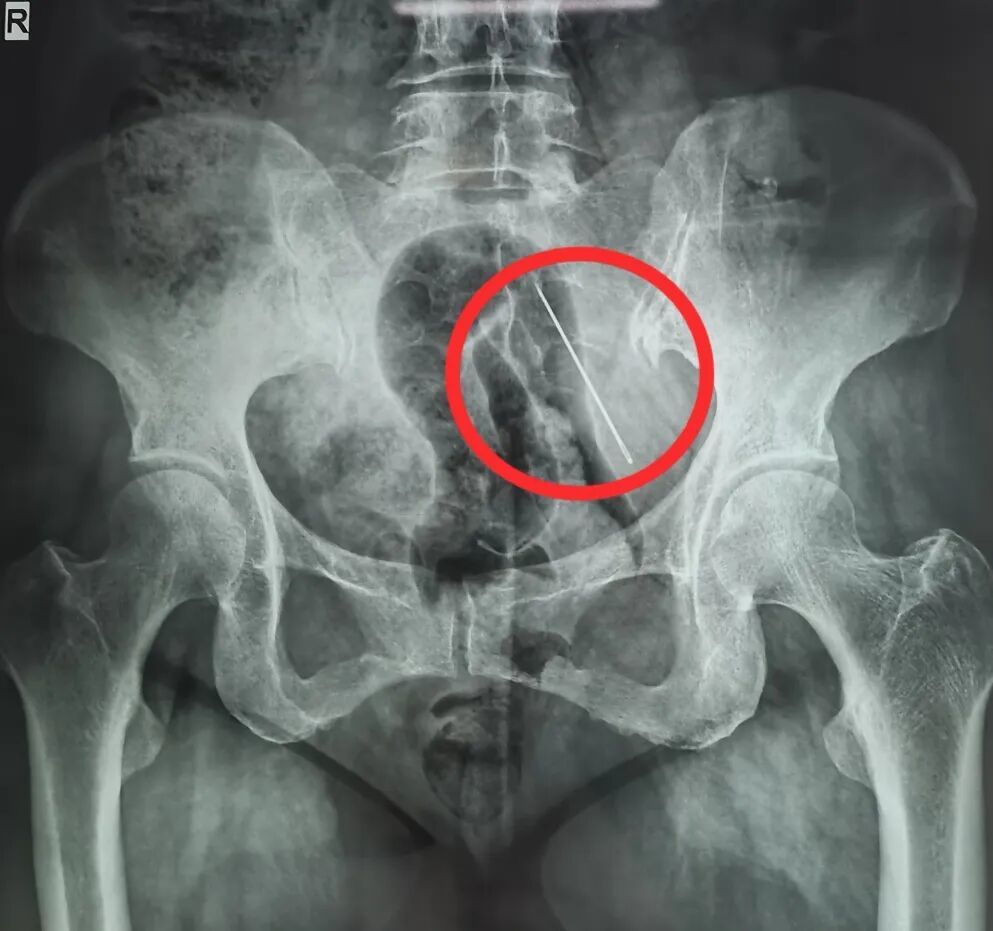

X光片显示张阿姨腹部内有异物

急诊医学科医生接诊后,当即安排她进行腹部CT和X线检查。检查结果清晰显示,张阿姨的腹壁内有一根4cm的异物,好在只是扎入脂肪层内,并未穿透掉入腹腔。

从张阿姨腹部内取出4CM钢针

由于情况紧急,张阿姨被转入普通外科进行急诊手术。赵伟主治医师采用了C型臂透视定位技术,在透视引导下,精准找到钢针所在位置,手术十分顺利,因为张阿姨腹部脂肪层较厚,钢针并未掉进腹腔,避免了腹腔内器官受损的风险,也大大降低了手术难度和术后并发症的可能。